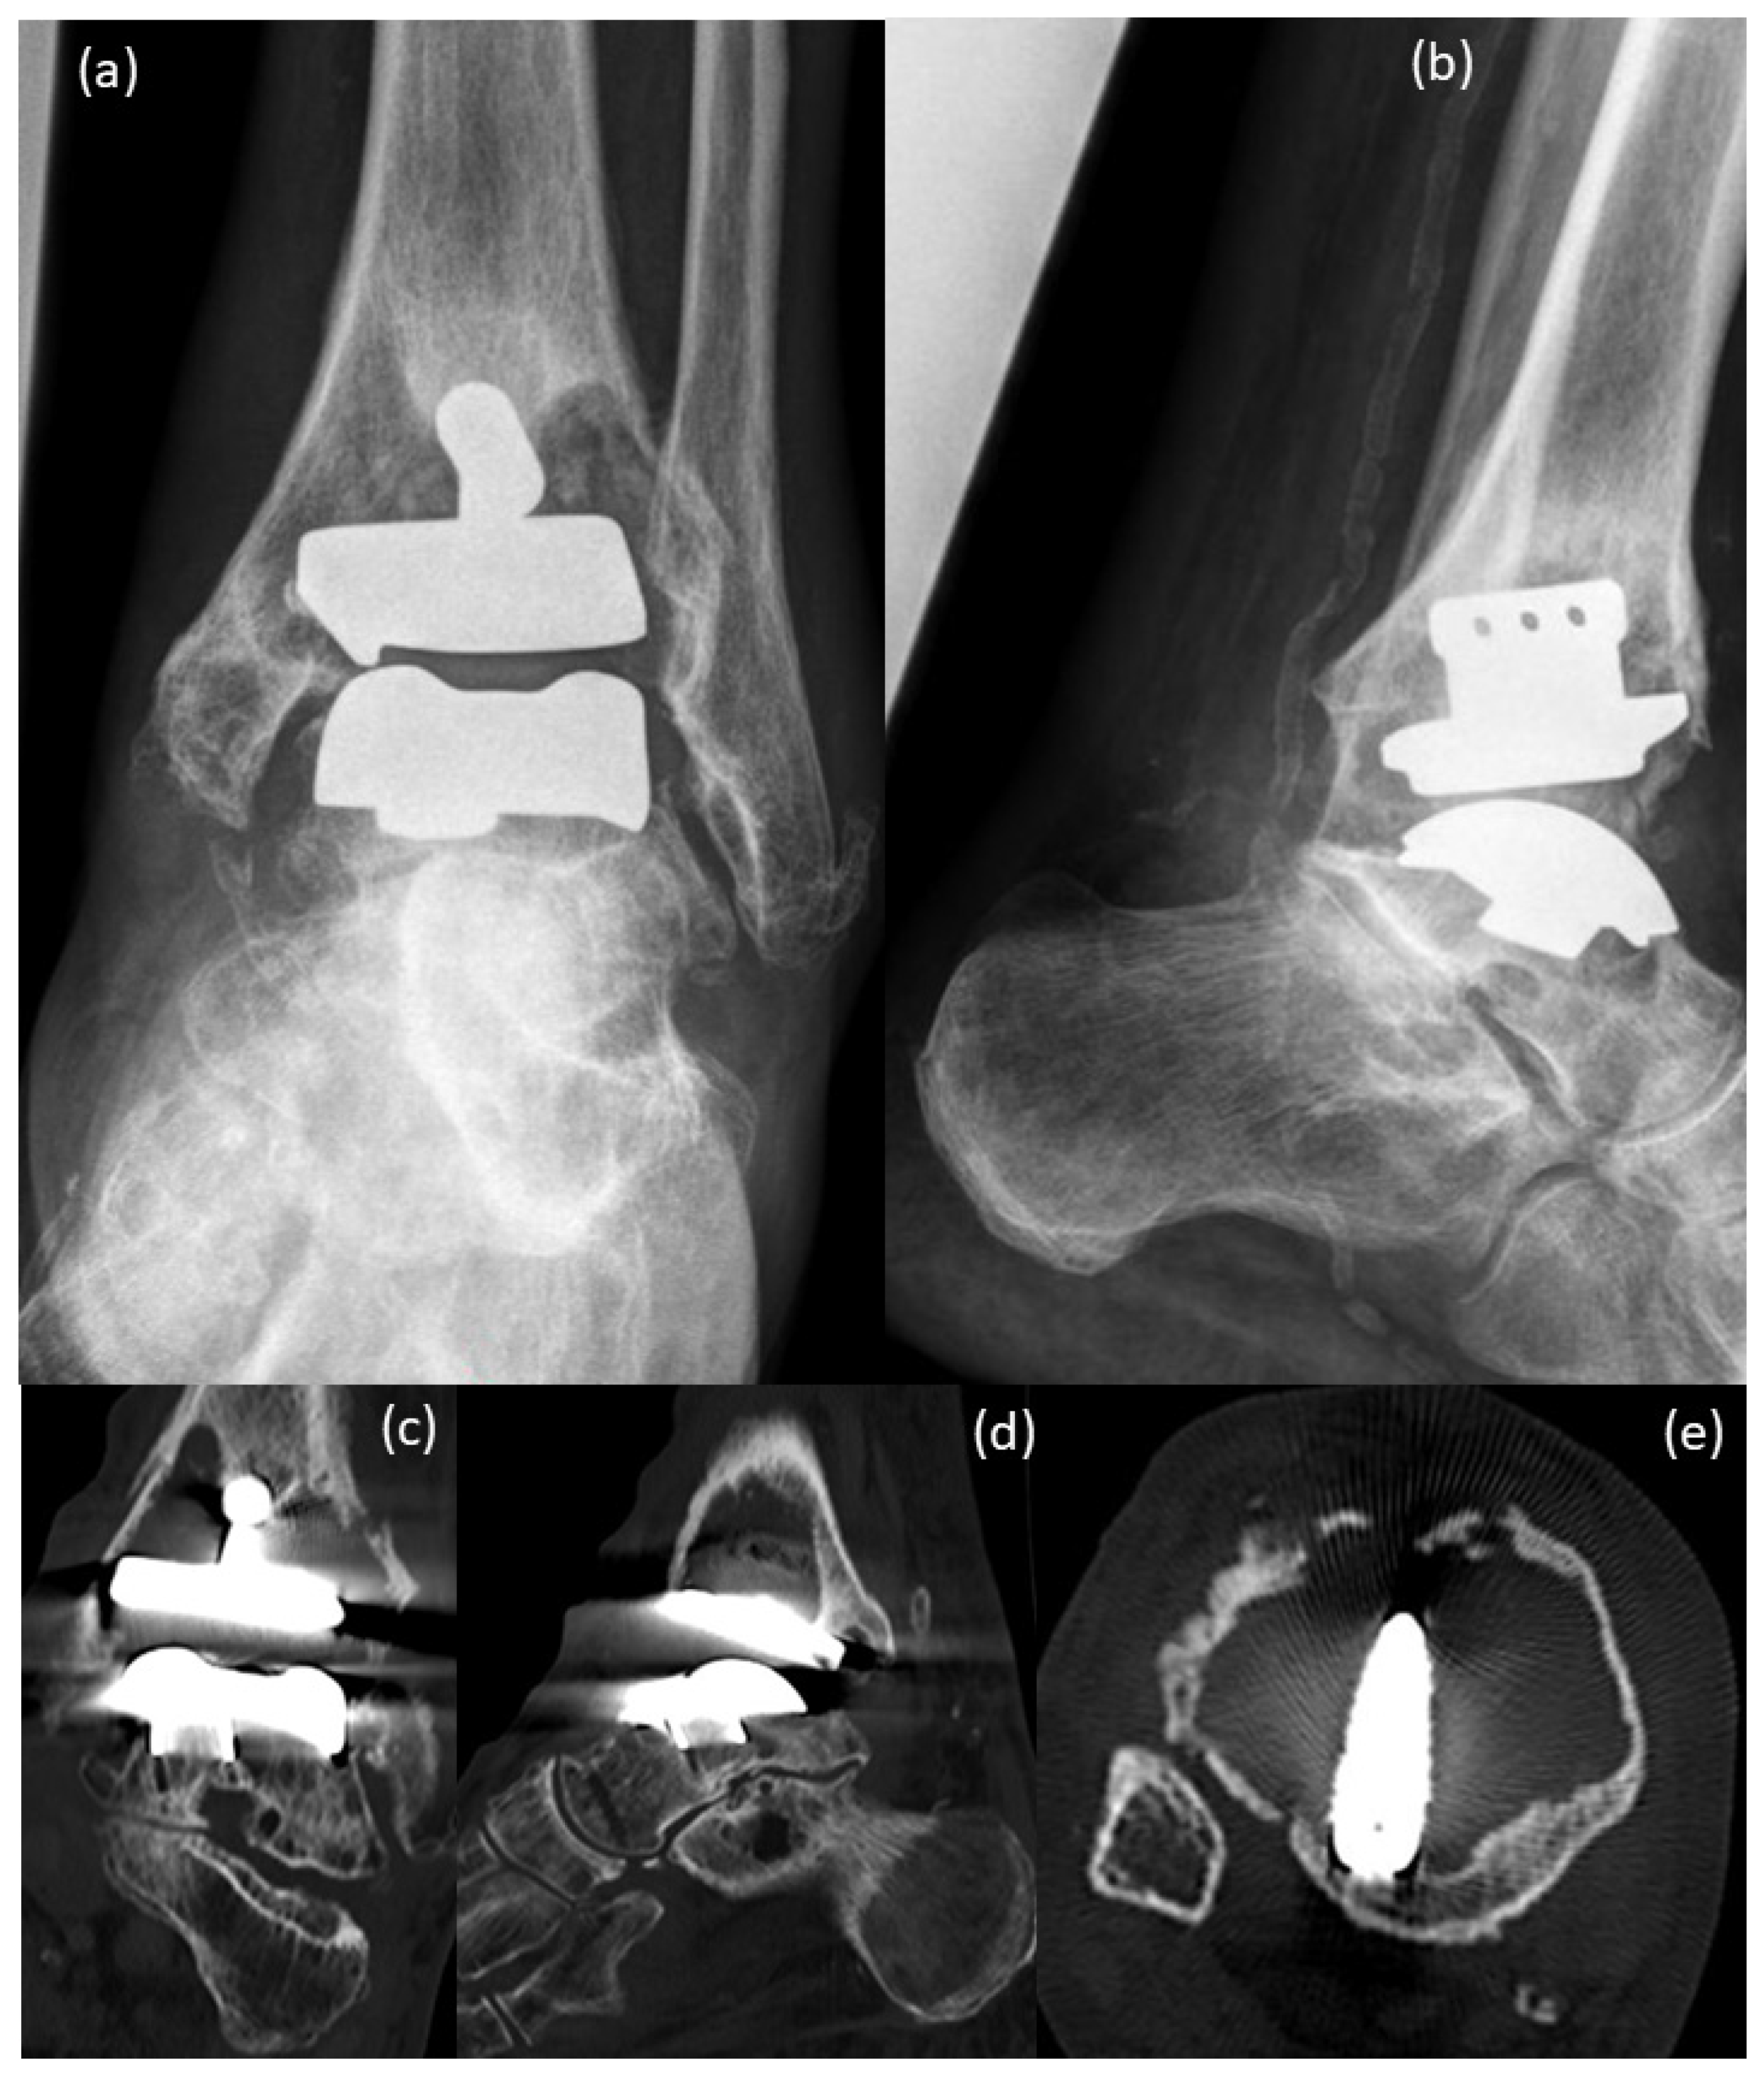

Figure 2.

Pre-surgical images 2020: (a,b) X-rays, (c–e) CT scans of the patient; (a,b) large cysts are present in the tibia and in the talus, compared to the images from the year 2016 (Figure 1), a massive increase in bone resorption and cyst formation is seen around the tibial component under involvement of the stem of the prosthesis. Therefore, an increasing tilt of the joint surface of the tibial component can be seen as a sign of incipient dislocation; (c–e) CT scans confirm the X-ray findings with massive bone resorption, pathologic fracture of the lateral tibial cortical surface and instability of the tibial prosthesis component.

The X-ray images from 2020, pre-surgery, showed large cysts in the tibia and in the talus (Figure 2a,b). Compared to the images of the year 2016, a massive increase in bone resorption and cyst formation was seen around the tibial component under involvement of the stem of the prosthesis. Consequently, an increasing tilt of the joint surface of the tibial component could be seen as a sign of incipient dislocation (Figure 2a,b). CT scans before surgery (Figure 2c–e) confirmed the X-ray findings with massive bone resorption, pathologic fracture of the lateral tibial cortical surface and instability of the tibial prosthesis component.